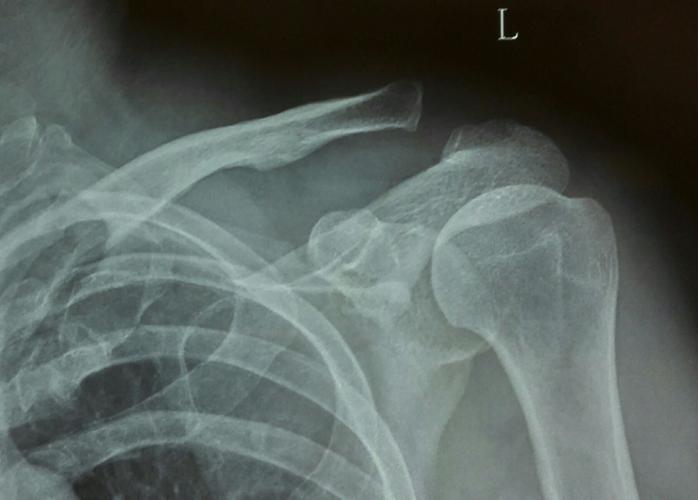

肩部正常x片图片

肩部正常x片图片,正常的肩关节x片图片

肩关节正位-x线图

求助,各位老师看看是否肩锁关节脱位?

左肩锁关节脱位endbutton固定

正常的肩关节x片图片

正常人肩部x光片